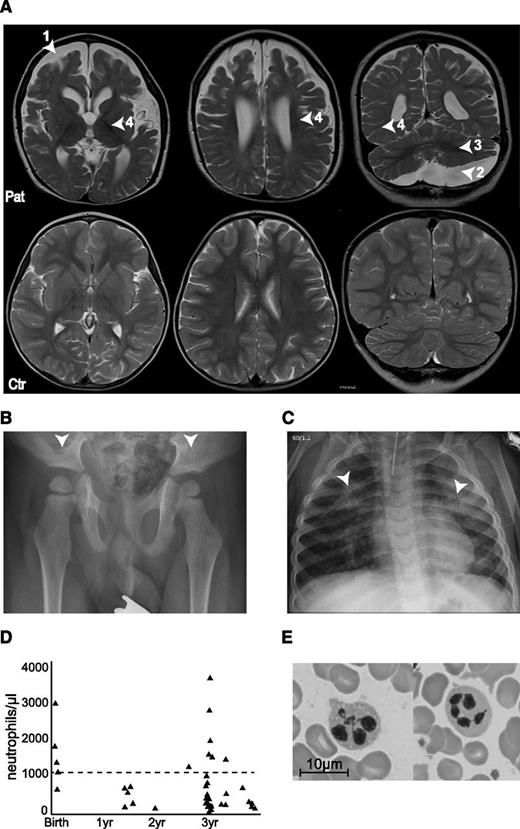

The index patient had early-onset seizures, severe developmental delay, dysmorphic features, and infection susceptibility associated with neutropenia; he was the first child of consanguineous Turkish parents (first cousins). The mother had secondarily generalized focal epilepsy that was treated until she was age 18 years and the father was healthy. A younger brother was affected by osteopetrosis caused by a homozygous TCIRG1 (OC116) mutation. At birth, the patient was microcephalic (length, 50th percentile; head circumference, 3rd percentile) with large, low set ears, retrognathia with a Pierre-Robin sequence, hypotelorism, and a flat philtrum. At age 1 week, he developed recurrent apneas followed by a focal seizure at age 11 days and increasingly dystonic movement patterns with truncal hypotonia. Within the first years of life, he developed spasms, tonic and myoclonic focal seizures, and generalized tonic-clonic seizures that occurred up to 30 times daily and were poorly controlled with multiple antiepileptic drug regimens. The electroencephalogram showed multifocal spike slow wave activity and no physiological differentiation. A hearing test revealed bilaterally reduced otoacoustic potentials and a reduced brainstem-evoked response audiometry. He made little developmental progress before his death at age 3.5 years and maintained general hypotonia, lack of head control with little spontaneous movement, and no ocular fixation. He had significant feeding difficulties. Oculocutaneous albinism was associated with poorly pigmented hair and intermittent nystagmus. Brain magnetic resonance imaging at age 3.5 years showed atrophy of the telencephalon and enlarged external and internal cerebrospinal fluid spaces as well as a large arachnoidal cyst in the posterior fossa. Furthermore, the myelination was insufficient for his age corresponding rather to that of a 15-month-old child. Cerebellar white matter was hypointense, which indicated myelin only projection fibers, and central parts of the supratentorial white matter were myelinated involving some subcortical domains but not U-fibers (Figure 1A). A hip radiograph showed flat acetabulae (Figure 1B).

Clinical phenotype of the patient. (A) Magnetic resonance imaging (MRI) scans of the brain at 3.5 years (upper row), with arrowheads indicating (1) atrophy of the telencephalon, (2) arachnoidal cyst in the posterior fossa, (3) insufficient myelination, and (4) enlarged external and internal cerebrospinal fluid spaces. The lower row shows MRI scans of a healthy 3.5-year-old child. (B) X-ray of the pelvis showing flat, dyplastic acetabulae. (C) X-rays of the chest showing chronic interstitial pneumonia. (D) Neutrophil counts over time. Dashed line at 1000 neutrophiles/µL represents the clinical limit for neutropenia. (E) Bone marrow smear showing hypersegmented neutrophils.

From age 8 months, he developed recurrent bronchitis and pneumonia. Chest x-rays revealed chronic interstitial pneumonia (Figure 1C). He had persistent hepatosplenomegaly and febrile episodes that were frequently associated with severe neutropenia (Figure 1D) but did not develop thrombocytopenia or anemia. Bone marrow showed moderate dysplasias (Figure 1E) with full maturation of all lineages. He had asymptomatic seroconversion to Epstein-Barr virus and cytomegalovirus. Abnormal bleeding was not noted. The patient died at the age of 3.5 years as a result of septic pneumonia.